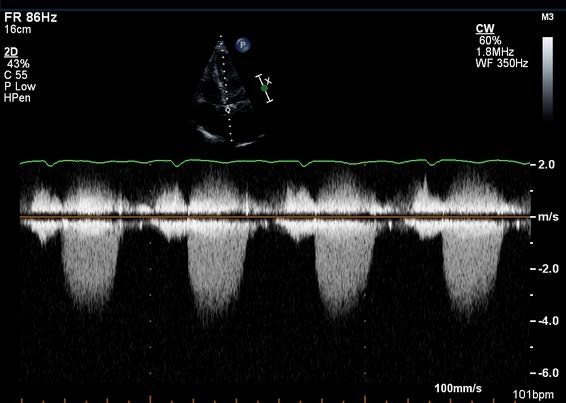

M-mode ultrasound: Uses a single beam path to display motion of structures over time.

Particularly useful for cardiac imaging (adult and fetal heart)

Displays structure position on the vertical axis versus time on the horizontal axis

An echocardiogram demonstrating M-mode application: the top shows the 2D cardiac view with the M-mode cursor line, while the bottom displays the resulting motion tracing over time.